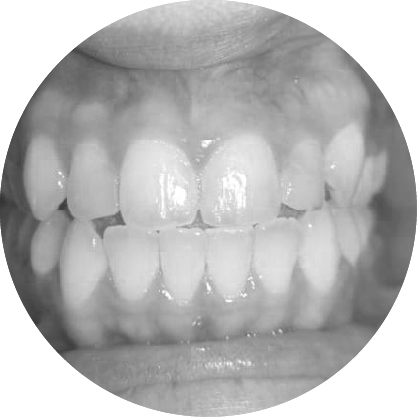

ฟันสบลึกเกิดขึ้นเมื่อฟันบนยื่นทับฟันล่างมากเกินไป หากปล่อยไว้โดยไม่รักษา อาจส่งผลต่อรูปลักษณ์และสุขภาพช่องปาก การรักษาทางทันตกรรมจัดฟันมีเป้าหมายเพื่อฟื้นฟูความสมดุลและการทำงานของฟัน เพื่อให้คุณมีรอยยิ้มที่มั่นใจ

ตัวอย่างในชีวิตจริง